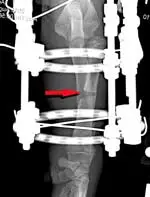

In this case, the treatment chosen was a partial closing wedge osteotomy (based on the CORA) and a gradual angular correction of the proximal radius via tensioning of a single olive wire positioned within a circular ring fixator, without the performance of an arthrotomy (Figure 3).

Figure 3: Frontal plane radiograph of the left antebrachium immediately after surgery showing the placement of the circular ring fixator on the limb with a single olive wire engaging the proximal radial segment. A closing wedge ostectomy has been completed at the level of the CORA (red arrow).